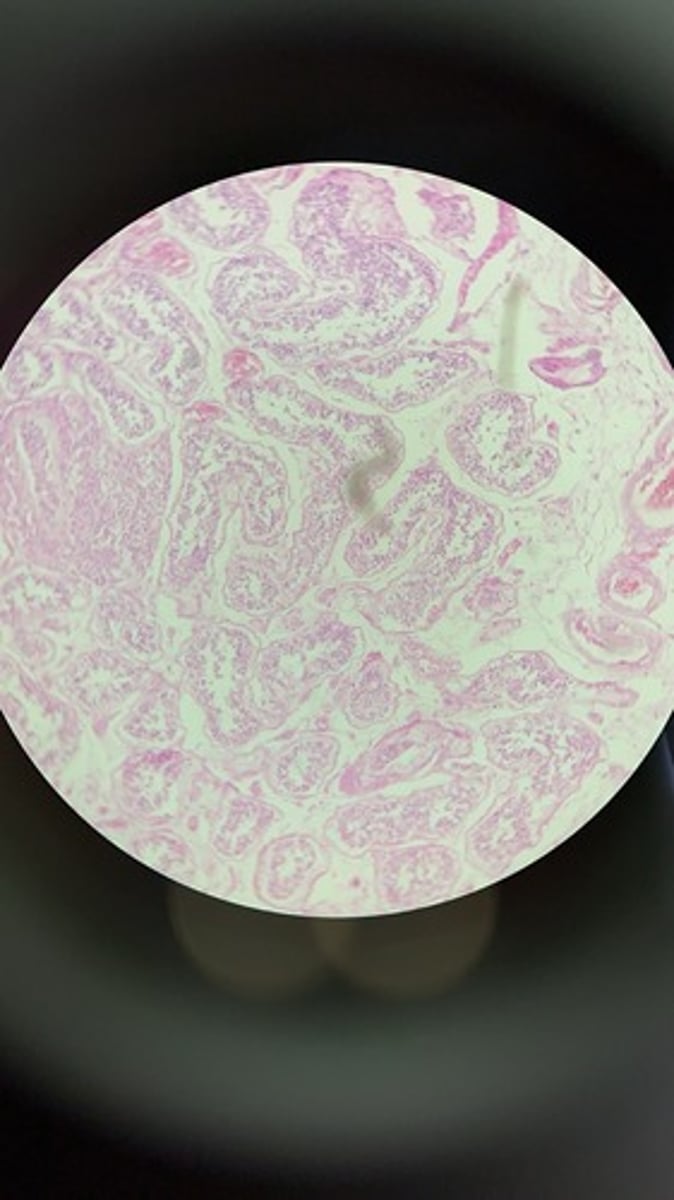

Prostate HE

Prostate HE

Prostate HE

Prostate HE